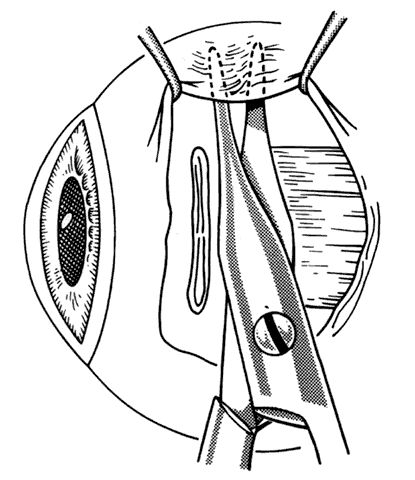

In some situations, a portion of a horizontal rectus may be left at the insertion site (Figs. 9 and 10). The muscle is usually split at the time of the initial procedure, and this can cause a shift of the distribution of force at the insertion and cause vertical misalignment. The pattern of the strabismus and the details of the previous surgery should provide clues to the problem and allow a logical approach for correcting the vertical deviation. Suspicions should be confirmed by careful dissection and exploration of the region of the muscle insertion. The importance of careful evaluation and elimination of mechanical restrictions cannot be overemphasized.4,10

Fig. 9. Residual exotropia or hypertropia can occur if a portion of the lateral rectus muscle is not recessed with the first procedure. To prevent this, care must be taken to incorporate all portions of the tendon when recessing an extraocular muscle.

Fig. 10. The pole test, or sweeping a Stevens muscle hook anterior to the insertion, will ensure that the entire tendon is on the Jameson muscle hook.